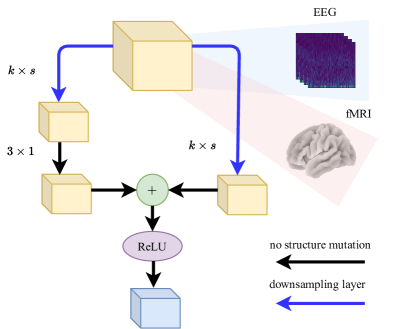

Mathematical operations, such as addition and subtraction, are performed over the EEG and fMRI feature representations, and , to map the original spaces onto encoded spaces that are identical in structure, and , respectively. This is performed in accordance with the methodology described in Appendix 0.A. To this end, architecture modules of Resnet-18 blocks is optimized using Calhas et al. [21] framework, which hyperparameterizes kernel and stride sizes, potentially differing from layer to layer. The heterogeneity of this convolutional layering structure is beneficial for the performance of the model according to Riad et al. [22]. Following, is processed by a densely connected layer with a linear activation to perform the decoding from the encoded representation onto the fMRI volume. Figure 1 illustrates the described neural processing pipeline. For the sake of simplicity, please consider .

The mean absolute error (MAE) is used as the loss function, , and the cosine distance between the latent representations of the EEG and fMRI was added as a regularization term, . MAE is known to be robust under limited data settings and the regularization term on latent representations forces the network to approximate the target representation at the earlier layers [29]. The regularization constant was set to and not optimized for the sake of proof of concept. Please recall the gradient computation illustrated in Figure 1.

Resnet-18 block configuration. The neural architecture specification (Equation 7) is to replace the downsampling blocks of the Resnet-18, illustrated in Figure 7. He et al. [48] defined kernel and stride sizes set as for all blocks. Note that, it is encouraged to use different kernel and stride sizes for the different layers [22]. Therefore, the variable assignments, of Equation 7, are used as the kernel and stride sizes.